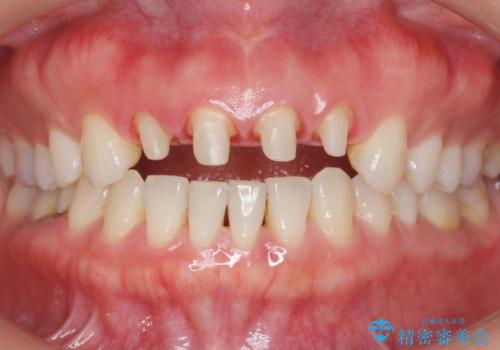

- 10年前に美容外科クリニックで前歯を治療したところ、あまりに不自然で逆にコンプレックスになってしまったことを主訴に来院された患者様です。

前歯4本の被せものは連結されており、不自然なだけではなく清掃性も悪く歯茎が著しく腫脹していました。

レントゲンを撮影したところ土台の植立も不十分であったため、土台からやりかえることにしました。

歯茎の腫脹が顕著であったため、適合の良いオーダーメイドの仮歯に変え、歯茎の状態が良くなるまで1ヶ月待ったのち型取りを行いました。